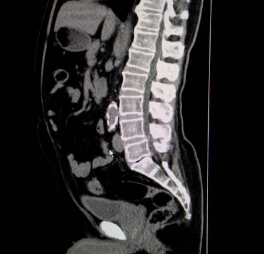

목 디스크는 경추 부위에서 발생하는 디스크 이상 중 하나입니다. 디스크는 척추 각 뼈 사이에 위치한 연골 조직으로, 척추를 보호하고 충격을 완화하는 역할을 합니다. 디스크는 외부 경계를 둘러싼 섬유성 껍질과 내부를 채우는 젤 형태의 핵으로 구성되어 있습니다. 목 디스크가 이상을 보면, 핵이 껍질을 뚫고 나와 인접한 신경을 압박하게 되어 목의 통증, 근경련, 무력감, 저림 현상 등의 증상을 유발할 수 있습니다. 목 디스크는 일상생활에서의 부상이나 과도한 스트레스 등에 의해 발생할 수 있으며, 적절한 치료 없이 방치하면 심한 증상을 유발할 수 있습니다.

목 디스크는 경추 부위의 디스크 이상 중 하나로, 인접한 신경을 압박하여 다양한 증상을 유발할 수 있습니다. 다음은 목 디스크의 주요 증상 5가지에 대한 상세한 설명입니다.